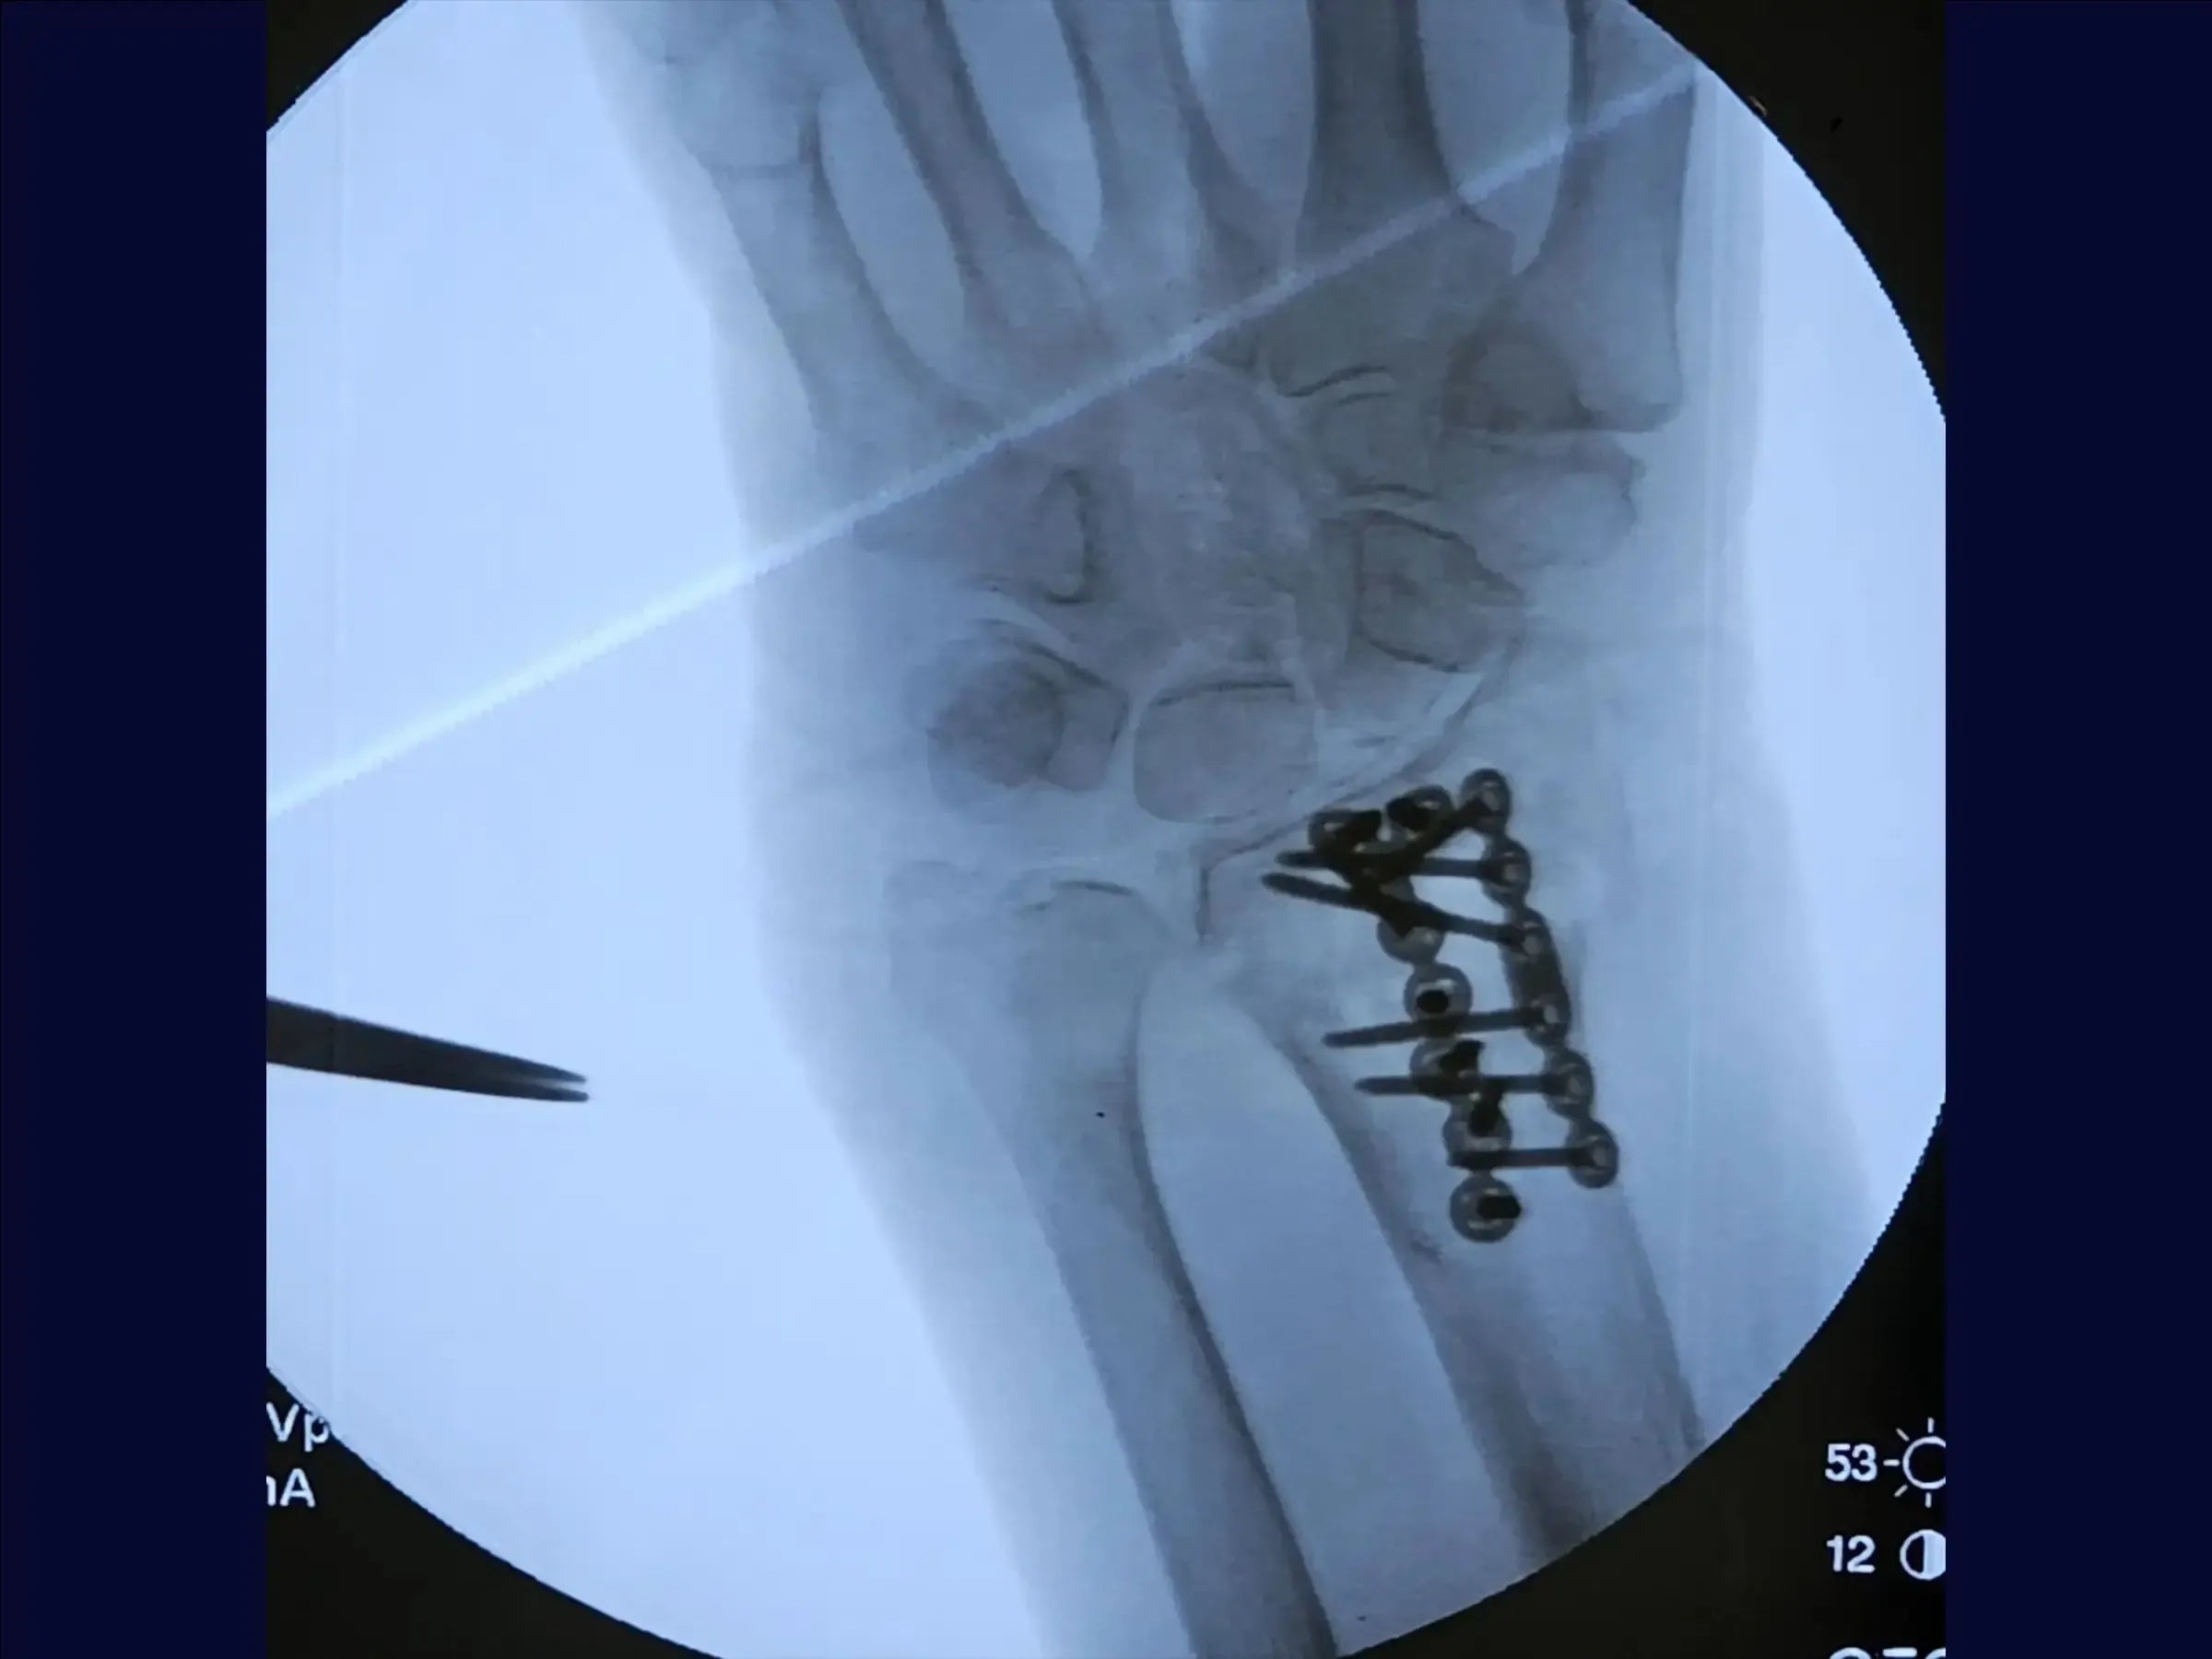

Domine o tratamento cirúrgico da fratura de Barton dorsal do rádio, que apresenta desvio articular e exige estabilização com placa através de uma abordagem dorsal. Este treinamento oferece uma imersão prática na técnica de redução, no acesso cirúrgico, na escolha do implante e na fixação, visando restaurar a anatomia e a função do punho, permitindo mobilidade precoce no pós-operatório, especialmente em pacientes idosos.

- Fixação e Verificações: Após a placa principal, o treinamento ensina a usar uma segunda placa de baixo perfil para fragmentos dorsais destacados, visando restaurar a região articular. São ensinadas verificações para assegurar que nenhum tendão esteja sob a placa e que os orifícios não violem a articulação.

- Fechamento e Resultados: As placas são posicionadas junto ao osso, garantindo tendões livres. O treinamento cobre a avaliação da redução em termos de comprimento radial, angulação e inclinação, e a liberação imediata da mobilidade em pacientes idosos no pós-operatório. O fechamento da pele encerra o procedimento.